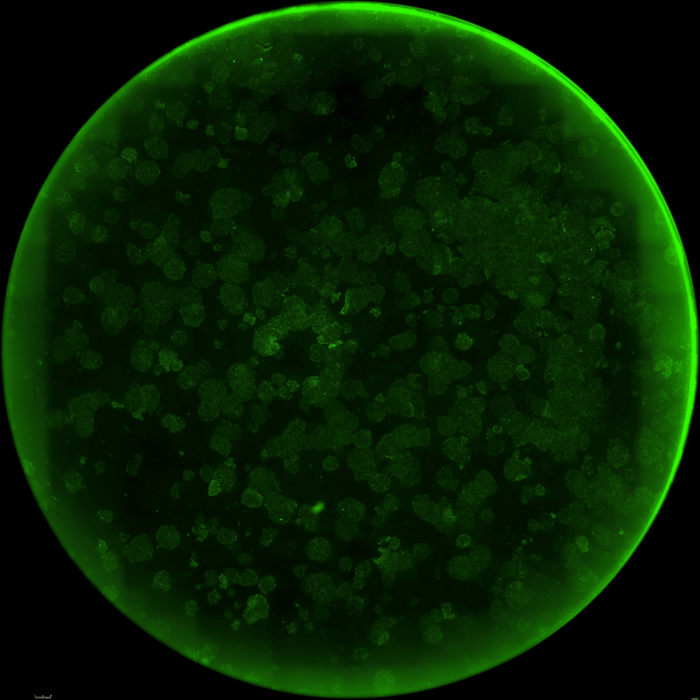

下面这三张图展示的是,OpenAI设计的蛋白质能更高效地诱导干细胞重编程:

使用RetroSOX与RetroKLF变体(结合OCT4, MYC)重编程10天后,出现了大量具有紧凑、圆形形态的集落,这是细胞迈向iPSC状态的典型特征

此外,研究团队在第10天通过碱性磷酸酶(AP)染色对RetroSOX和RetroKLF变体进行了验证。

结果显示,形成的细胞集落不仅表达晚期多能性标记物,还表现出强大的AP活性,这是细胞具备多能性的有力标志。